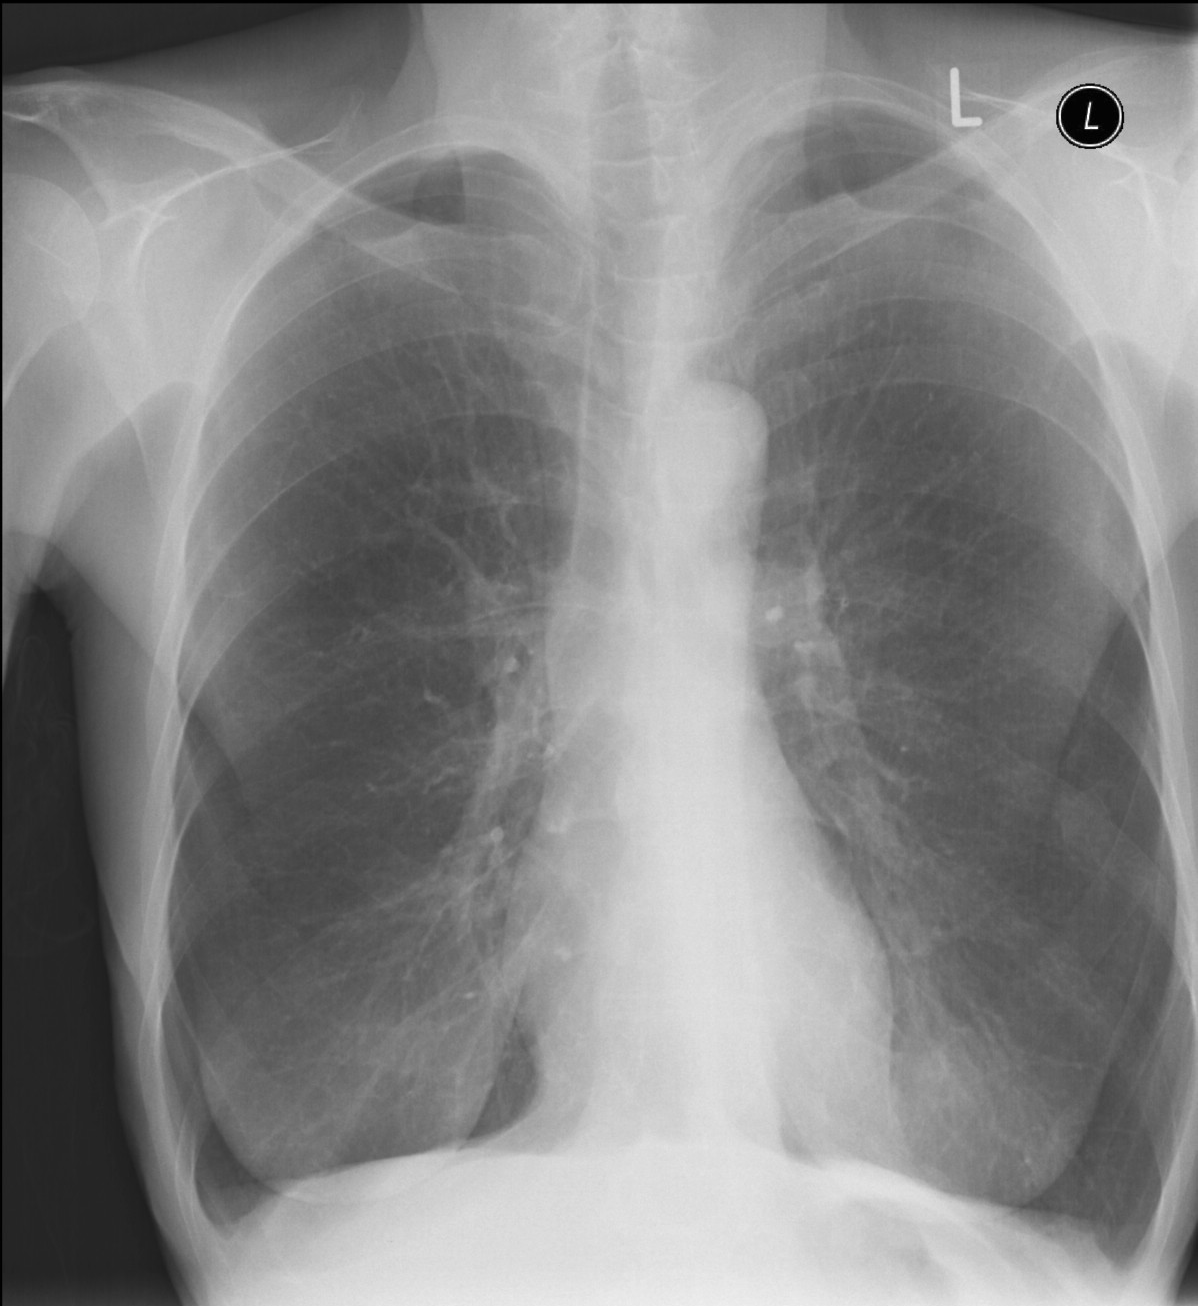

19. Tuberculosis, bidirectional chest radiographs and HRCT. (coronal reconstruction)

75 year old man: hx of hypertension, smoking. Symptoms: dyspnea, productive cough. Moist rales of auscultatory findings above the LLL, tension irritability in the level of lower dorsal spine.

a.) Chest radiograph, bilateral: Mild increased vascular markings. Extensive patchy lobar infiltration in the RUL Previous TB specific lesions in the left apex. The diaphragm contour is blurry on the right side (appr. 4 finger-wide pleural effusion). Cardiomegaly. Medium large dilated sclerotic aorta.

b.) HRCT: Reticular pattern of 10x10x5 cm area in the right apex (1st segment), (septal thickenings), mosaic-like ground glass opacity in the righ apex. Subpleural total atelectasis (mainly 1st segment): irregular mainly nodular soft tissue streak associated with the pleura (max. appr. 1 cm thickness). Some tiny subpleural emphysematous bullae in the right apex.